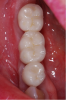

Fig 14. Final restoration in place, buccal view.

Figure 14

Fig 15. Final restoration in place, occlusal view.

Figure 15

Delivery

Figure 11 and Figure 12 depict the presentation of the model and restoration for delivery. The case was tried in with minimal adjustments, as is typical with most digital cases.20 One consideration at seating was the gingival collar at tooth No. 31 on the buccal. At initial seat, the tissue was noted to be recessed (Figure 13). The author was left with the options of seating temporarily or retuning to the laboratory to address the affected area. It was decided to seat temporarily and allow the tissue to respond. After 3 weeks the patient returned and the tissue had adapted very well. The decision was made to seat more permanently.

The temporary material was removed, and the access holes were cleaned with a cotton pellet and isopropyl alcohol. The screw torque was verified to be 35 Ncm (minimum 15 Ncm), as dictated by the manufacturer.24 It is critically important to verify the torque values prior to torqueing the abutment, as each implant and abutment manufacturer has a recommended torque value.

Following the torqueing of the implant, the author used a “sandwiching technique” to ensure esthetics of the access hole. Although this is not necessary, patients seem to appreciate the attention to detail and the highly esthetic result. The technique is as follows: (1) place teflon tape directly over the screw; (2) etch the internal surface to the external margin of the access hole; (3) apply universal bonding agent to access up to occlusal margin, then cure; (4) bulk fill composite (for deep access holes) to within 2 mm of access hole, then cure; (5) apply opaqueing resin to 1 mm below the access hole; (6) completely cover the access hole with nanocomposite; (7) polish.

The final restoration is shown in Figure 14 and Figure 15. The patient was extremely pleased with both the result and the process.